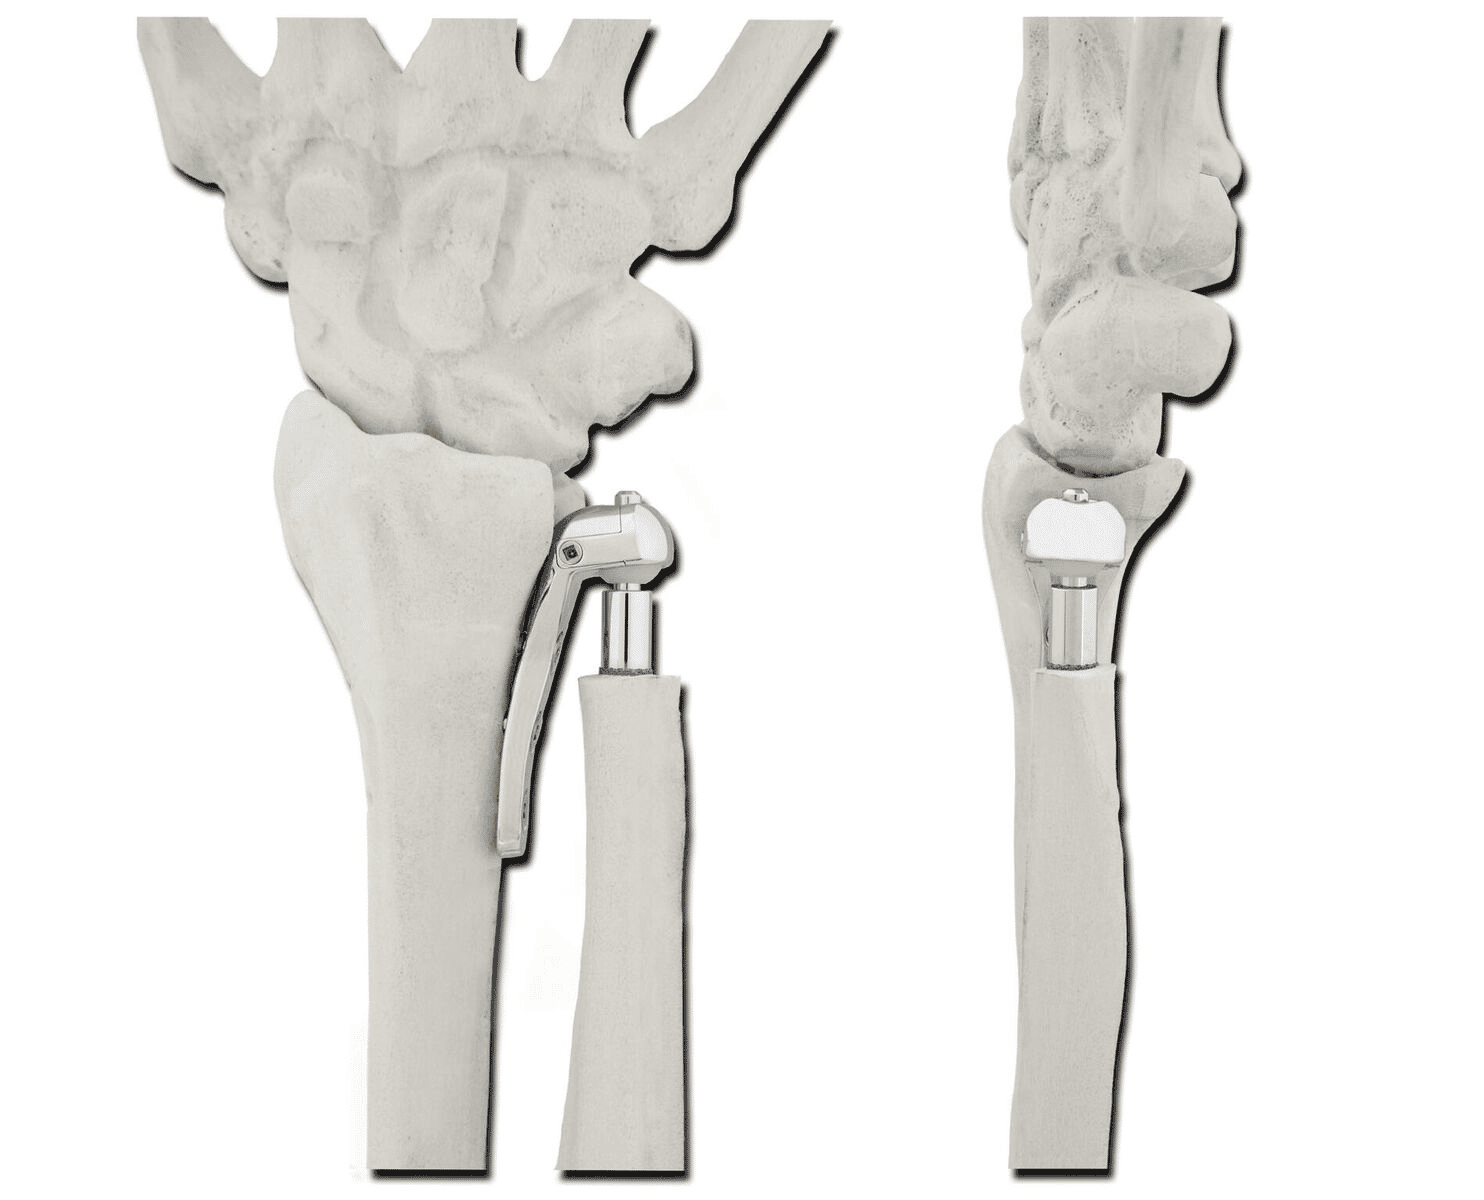

In uw pols is in het gewricht tussen het spaakbeen en ellepijp (het DRUJ) artrose ontstaan. De oorzaken hiervoor zijn: niet anatomisch geheelde fracturen van de pols, (onbehandelde) bandletsels van de pols, instabiliteit, kraakbeenslijtage, reuma of groeiafwijkingen (Madelung) van de pols.